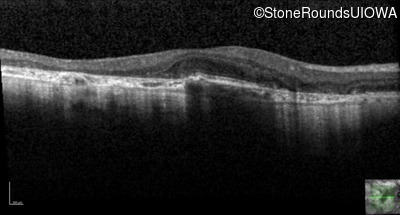

AR Stargardt Disease (IIA)

Age at visit: 51 years

This 51 year old woman first experienced some abnormality in her distance vision when she was 27 years old. She feels that her vision has been stable since that time.

Diagnosis & molecular findings

Disease Gene Allele 1 variant(s) Allele 2 variant(s) Inheritance mode

AR Stargardt Disease ABCA4 Gly1507Arg GGG>AGG IVS42+1 G>A AR